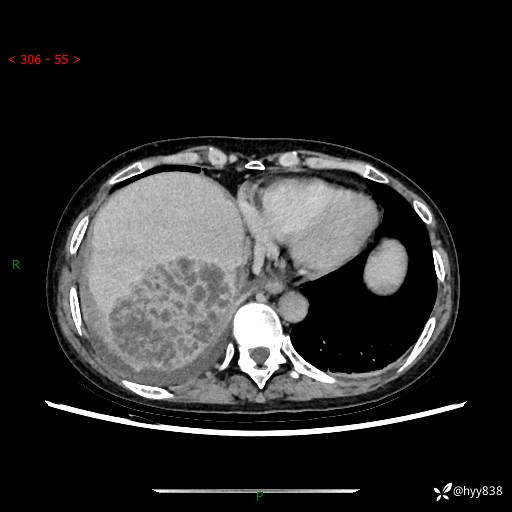

病例老年女性,发热来诊。如此“蜂窝煤”,治疗很棘手---结果公布~

性别:女

年龄:53岁

简要病史:发热(门诊急诊患者)

上腹部CT平扫